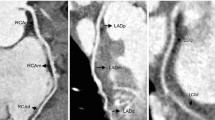

Since the early 1980s, the arterial switch operation has become the standard corrective technique for transposition in the absence of significant associated lesions like pulmonary stenosis [63]. The procedure re-creates physiological ventriculo-arterial concordance by transecting the great arteries and translocating them to the opposite root, with rearrangement of the pulmonary arteries anterior to the aorta (Lecompte maneuver). Translocation of the aorta implies mobilization and reimplantation of the coronary arteries, which are excised with a small cuff of aortic wall to be resutured into the neo-aortic root, with a somewhat stretched course compared to their original position (Fig. 13). In the early experiences, coronary manipulation was the main surgical issue, leading to coronary insufficiency and high perioperative mortality. Coronary transfer techniques have greatly improved since, with a substantial drop in hospital mortality, although the long-term success of the operation remains strictly dependent on the patency of the reimplanted coronary vessels. Most coronary events occur in the first 3 months after surgery [57] and are usually related to kinking or other types of anatomical obstruction to coronary perfusion. Late complications have an incidence of up to 10% and can lead to myocardial ischemia or infarction [64]. Imaging of coronary anastomoses is recommended in symptomatic children, as well as at least once in asymptomatic patients during adolescence or early adulthood [54]. Although catheter angiography is still the gold standard for coronary lesions, CT represents a reasonable alternative (Fig. 14), providing high-resolution imaging and reducing both the need and the risks of invasive studies such as coronary ostium alteration during catheter placement [65].

Transposition of the great arteries after arterial switch operation in a 12-year-old girl. a–d Anterior oblique volume-rendered (a), curved planar reformation (b, c) and axial maximum-intensity projection (d) CT images show that the right (arrow) and left (arrowhead) coronary arteries are patent at the site of reimplantation. Note the typical anterior position of the pulmonary trunk (asterisk) relative to the aorta from the Lecompte maneuver

Coronary complication after arterial switch operation in a 6-year-old girl. a Posterior volume-rendered CT image demonstrates that the dominant left circumflex artery is not opacified at the site of reimplantation (arrow). b–d Vertical (b) and horizontal (c) long-axis and mid-ventricular short-axis (d) CT reconstructions of color-coded perfusion maps confirm the finding by revealing a large transmural perfusion defect (arrowheads) in the infero-lateral wall, consistent with ischemic/infarcted myocardium

The Ross, or Ross-Konno, procedure is an alternative to prosthetic valve replacement in children with aortic valve stenosis [66]. During surgery, the pulmonary valve is translocated to the aortic position and a homograft conduit is placed to reestablish continuity from the right ventricle to the pulmonary artery. As with the arterial switch operation, the coronaries need to be excised from the native aortic sinuses and reimplanted into the neo-aortic root, but complications are less frequent because the vessels are reattached almost in their native position rather than being stretched (Fig. 15). Over recent years, other surgical operations implying coronary manipulation, such as the Nikaidoh procedure for people with transposition, ventricular septal defect and pulmonary stenosis, are becoming more common, expanding the potential indications for coronary artery follow-up by CT [52].

Coronary complication after Ross operation in a 7-year old boy. a-c Left anterior oblique volume-rendered (a), oblique axial maximum-intensity projection (b) and curved planar reformation (c) CT images show that the coronary arteries are patent at the site of reimplantation (curved arrows) but the proximal portion of the left anterior descending artery is suboccluded (straight arrow). d Horizontal long-axis reconstruction documents a subendocardial perfusion defect in the septum and left ventricular apex (arrowheads). e Similar MRI late-gadolinium-enhancement image in the horizontal long-axis plane demonstrates a subendocardial infarct at the same level (arrows)